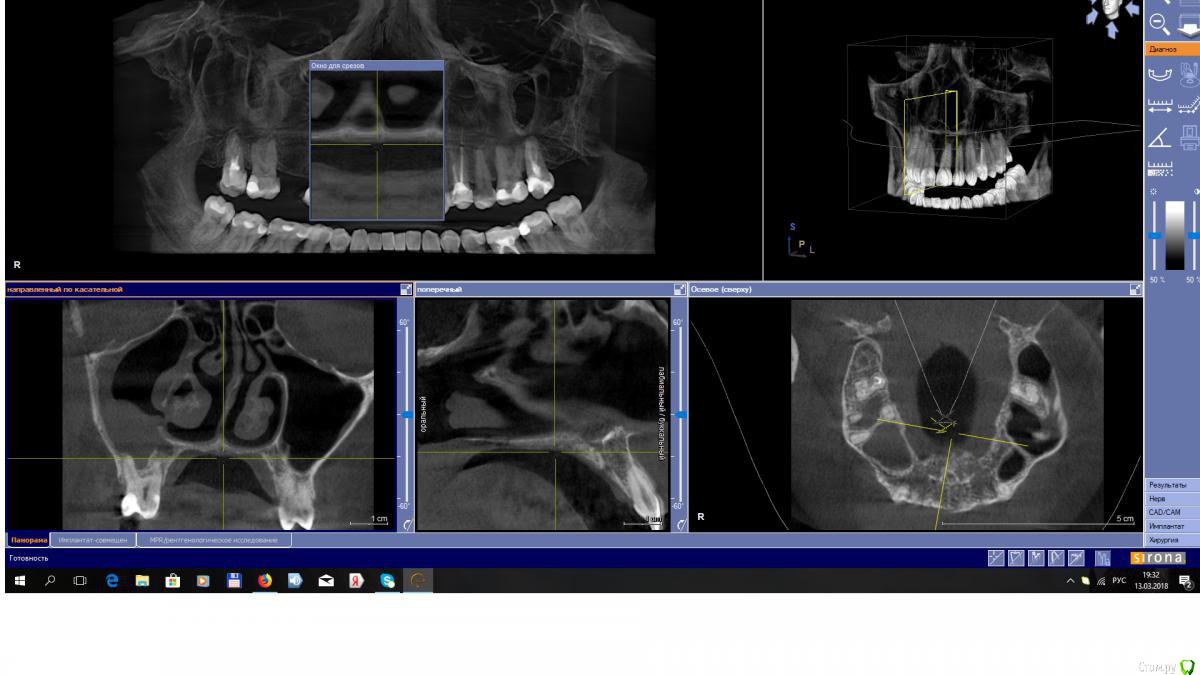

EEcho Опубликовано 13 марта, 2018 Автор Поделиться Опубликовано 13 марта, 2018 Я то же сначала подумал о 16, но ЭОД показала норму, 17 резорциненый уже много лет и без изменений в апикальных тканях.снимки противоположной пазухи прилагаю. Про грибы как то не подумал, с ними ни разу не сталкивался, Спасибо!!! Ссылка на комментарий